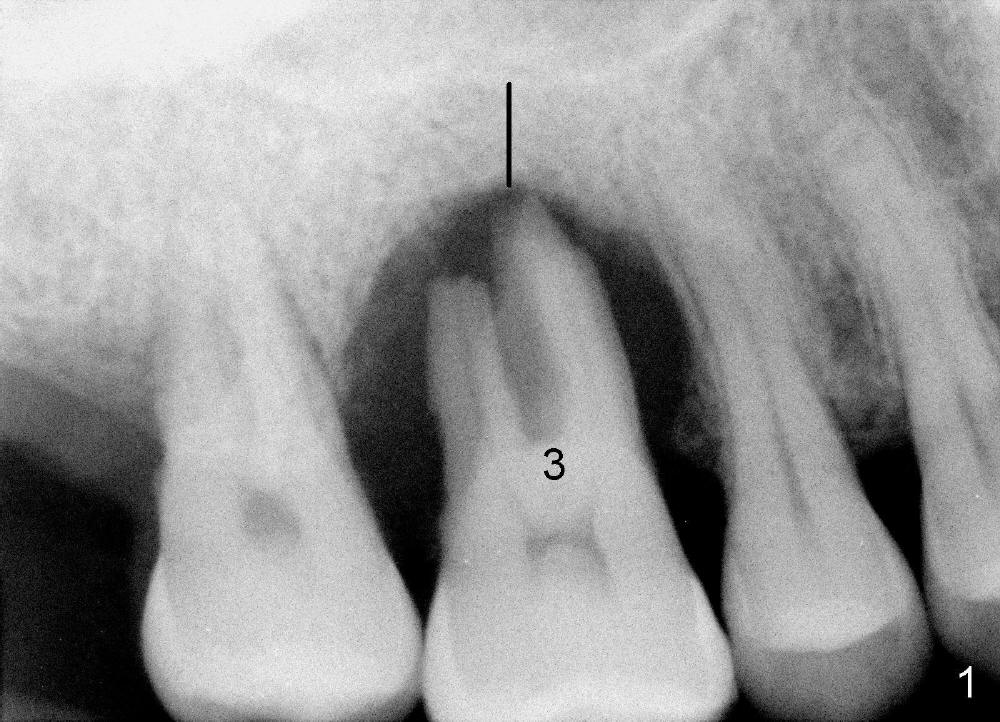

The upper right 1st molar of a 48-year-old man has severe perio endo disease (Fig.1 #3); the bone height for immediate implant (Fig.2) is about 3.5 mm (Fig.1 vertical line). There is a buccal (Fig.3 B) abscess (*); the palatal (Fig.4 P) root is exposed. After extraction, the socket available for immediate implant (Fig.5,6 S) is buccal (without septum), whereas the apex of the palatal root is far away from the main socket. In fact there is an advantage: the socket is smaller. Osteotomy is created in the main socket as palatal as possible, using osteotomes, reamers and taps (Fig.7 T). The sinus floor is lifted (Fig.7 ^). When 7x17 mm implant is placed (Fig.8 I), the insertion torque is >60 Ncm. The remaining socket (Fig.8 *) is to be packed with mixture of autogenous bone, allograft and synthetic bone (Osteogen) (Fig.9,10 <). Immediate insertion of an abutment (Fig.8-10 A) helps retain perio dressing (Fig.11,12). No collagen membrane is used in this case to cover the bone graft before placement of perio dressing. Postop the patient cannot tolerate oral Amoxicillin because of stomach upset. The dose is reduced. Two weeks postop, the perio dressing is stable, but discolors (Fig.13). When the dressing is removed, the buccal bone graft is exposed, which is not abnormal. What is unusual is discoloration (Fig.14). The significance of the latter is not revealed until 3 months postop when the patient remains asymptomatic, but there is an apical fistula (Fig.15 <). There is a communication between the fistula and the buccal sulcus of the implant: water passing freely. Based on the position of the buccal plate of the neighboring teeth (*), the buccal plate of the implant should be lost, which is consistent with finding of PA (Fig.16, as compared to Fig.8). Guided bone regeneration seems necessary.